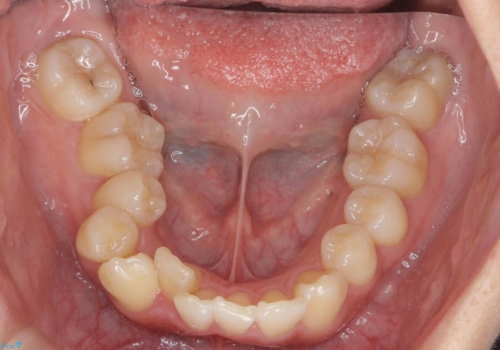

右の上下の混雑が激しく、通常は上下左右4本抜歯も相当する症状でした。

右下の臼歯が内側に倒れこみ、小臼歯部分はすれ違い咬合、大臼歯も反対咬合となっていました。

歯の大きさを計測したところ、下の歯がとても大きく、4本抜歯したとしても奥歯のかみ合わせを交互にするのが難しい状態でした。

この状態からうまく治療ができれば右下を頬側に起こすことができればある程度スペースが確保できそうでした。

下については、まずは動かして起こしてみて抜歯の本数は治療をすすめながら1本、右上下2本、上下左右4本の選択肢のうちどれかになるという方針としました。